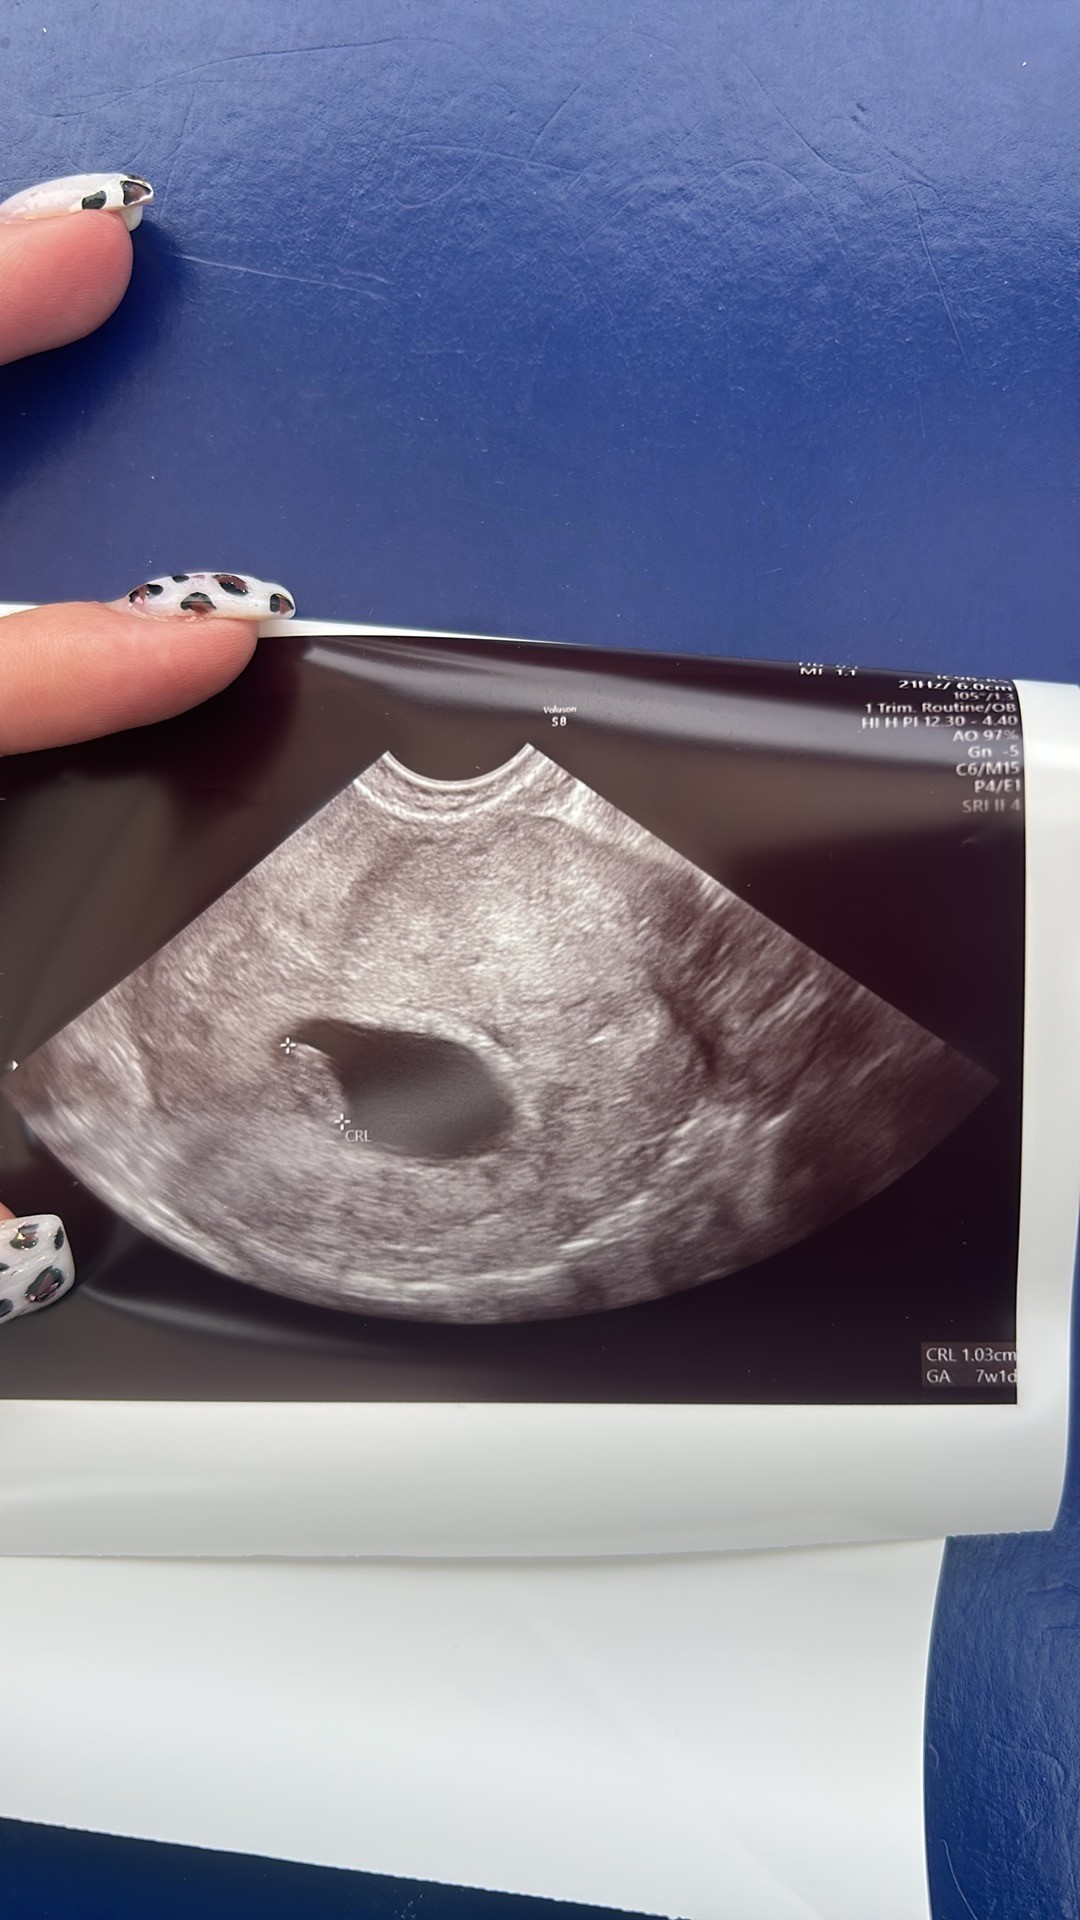

Ja po środku widzęNa pewno będzieja dostałam tylko takie zdjęcie i ledwo widać ten pęcherzyk

a przynajmniej ja nie widze